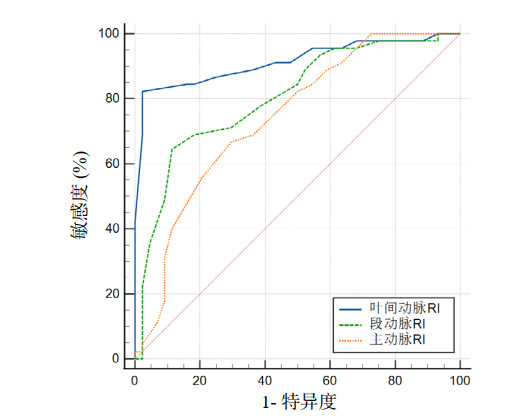

叶间动脉RI值的曲线下面积大于段动脉RI值、主动脉RI值(P < 0.05);叶间动脉RI值的敏感度、特异度均高于主动脉RI值(P < 0.05);叶间动脉RI值的敏感度高于段动脉RI值(P < 0.05),特异度差异无统计学意义(P > 0.05);叶间动脉RI值的约登指数大于段动脉RI值、主动脉RI值(见表 3、图 4)。叶间动脉RI与IAP的相关性高于段动脉RI值、主动脉RI值(见表 4)。对三个指标进行多因素Logistic回归分析,结果显示肾叶间动脉RI值是预测IAH的独立危险因素(P < 0.01)(见表 5)。

| 变量 | 截断值 | AUC(95%CI) | 敏感度 | 特异度 | 约登指数 |

| 叶间动脉RI | 0.698 | 0.914(0.835, 0.977)a, b | 0.822ab | 0.977a | 0.799 |

| 段动脉RI | 0.675 | 0.805(0.713, 0.896)a | 0.644 | 0.886a | 0.530 |

| 主动脉RI | 0.665 | 0.741(0.638, 0.845) | 0.667 | 0.705 | 0.372 |

| 注:a与主动脉RI相比,P < 0.05;b与段动脉RI相比,P < 0.05 | |||||

| 图 4 肾动脉不同节段RI值的ROC曲线图 Fig 4 ROC curve of RI values in different segments of renal artery |